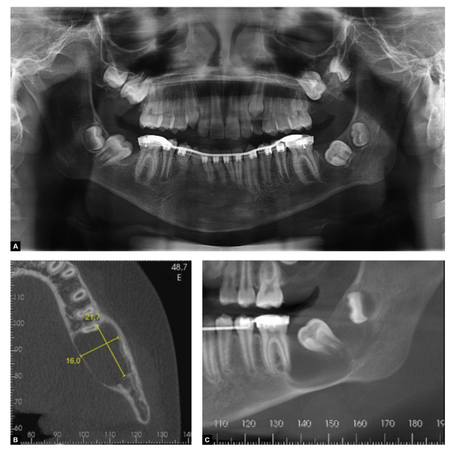

Introduction: Facial malignancies treated with surgery usually result in significant anatomical defects. Titanium is the gold standard, but its high cost limits accessibility. PMMA emerges as a cost-effective alternative, with good efficacy when associated with 3D planning. Case report: A patient, who underwent maxillectomy and radiotherapy 4 years prior for squamous cell carcinoma of the palate, presented with an extensive maxillary defect. 3D planning, stereolithography with ABS polymer, and a custom-made PMMA implant molded in a muffle were utilized. The surgical approach was via a...

Introduction: Facial malignancies treated with surgery usually result in significant anatomical defects. Titanium is the gold standard, but its high cost limits accessibility. PMMA emerges as a cost-effective alternative, with good efficacy when associated with 3D planning. Case report: A patient, who underwent maxillectomy and radiotherapy 4 years prior for squamous cell carcinoma of the palate, presented with an extensive maxillary defect. 3D planning, stereolithography with ABS polymer,...